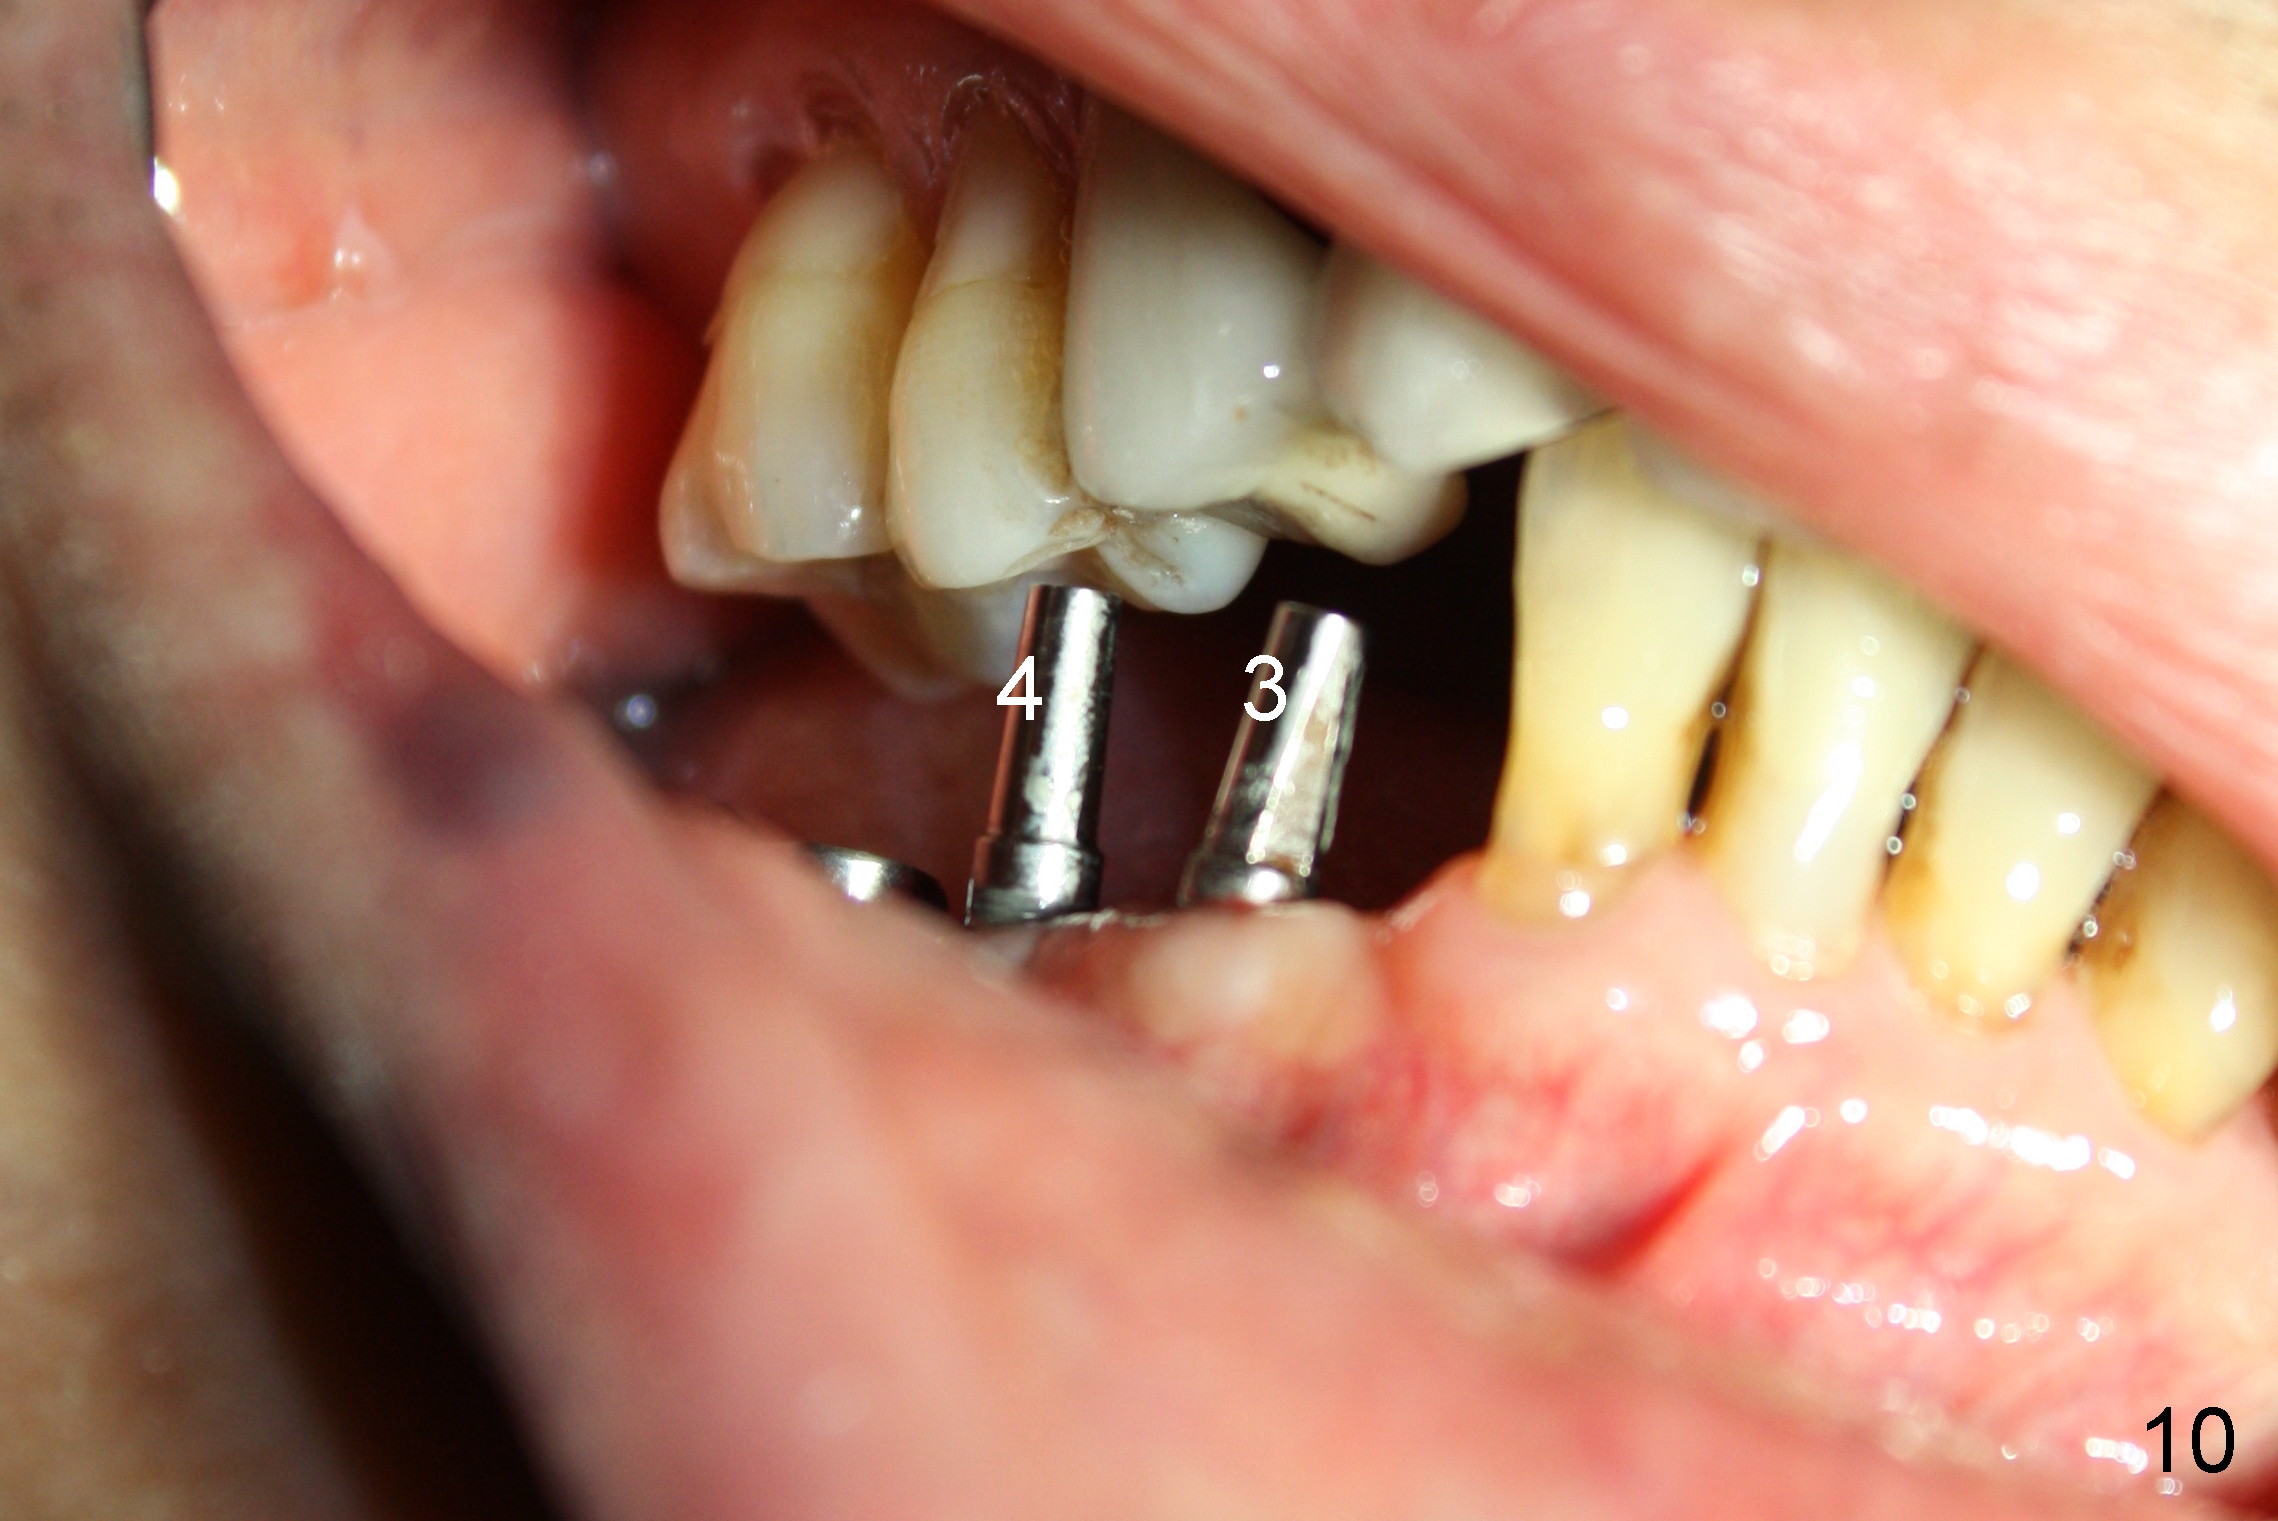

The lower right bridge (from canine (Fig.2: 3) to 1st molar (Fig.1: 6)) fails while a 77-year-old man is undergoing chemotherapy for urinary bladder cancer. The abutments of the bridge are extracted without plan for implants (Fig.4). Four months later, the patient returns for implants (Fig.3), but the ridge is narrow (Fig.5). While 2 of 3x14 mm 1-piece implant are placed at the canine and 1st bicuspid sites, 2 piece ones at the 2nd bicuspid and 1st molar sites (Fig.6: 3.5x11 mm, 5x14 mm). Soft (Fig.7-10) and hard (Fig.11) tissues heal 1 week (Fig.7) and 4 months (Fig.8-11). There is minimal bone resorption 1 year 7 months post cementation (Fig.12,13, non-splinting). It appears that narrow diameter implants are a valid solution to narrow ridge at the sites of the lower canine and premolar. As long as there are enough implants for function, the crowns are not necessary to be splinted. Surprisingly, the patient starts flossing after implant restoration. Retrospectively an immediate provisional bridge should have been fabricated.